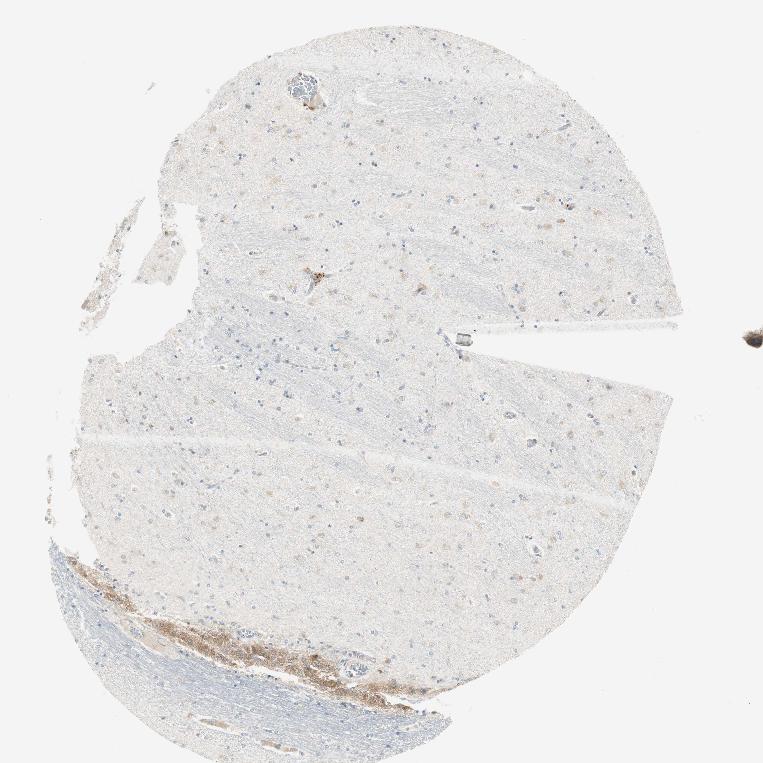

HIPPOCAMPUS - Antibody stainingi

Antibody staining in the annotated cell types in the current human tissue is reported as not detected, low, medium, or high, based on conventional immunohistochemistry profiling in selected tissues. This score is based on the combination of the staining intensity and fraction of stained cells.

Each image is clickable and will lead to virtual microscopy that enables deeper exploration of all samples and also displays staining intensity scores, fraction scores and subcellular localization as well as patient and tissue information for each sample.

Antibody HPA005715

Glial cells Low